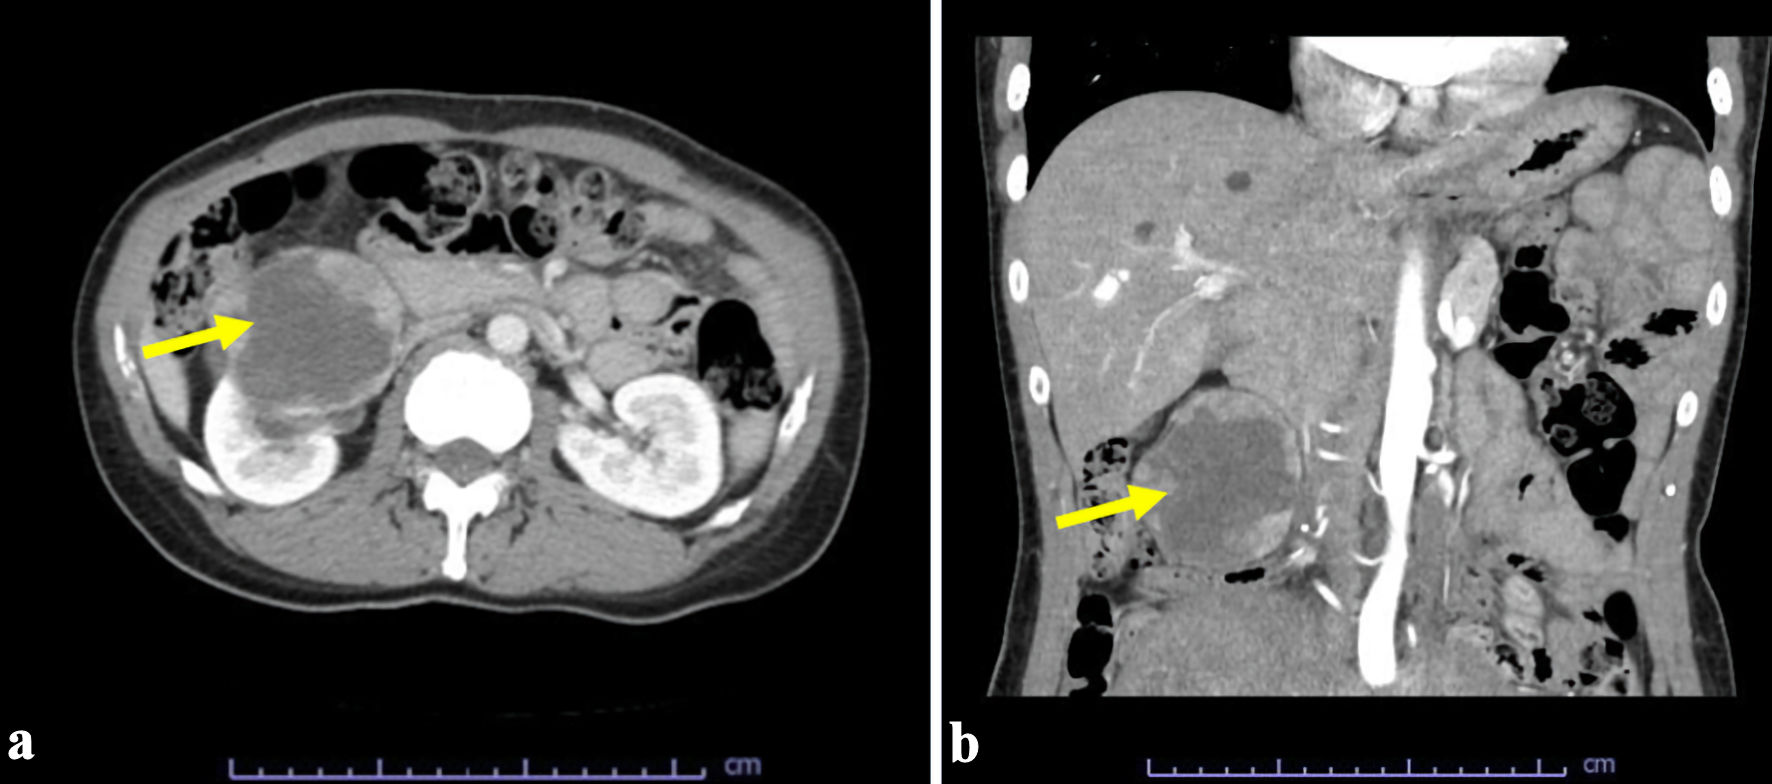

A 45-year-old woman, with multiple uterine myomas and a herniated disc visited the Emergency Department because of severe leg pain. Contrast-enhanced computed tomography (CT) of the abdomen and pelvis revealed a tumor in the lower pole of the right kidney (Fig. 1).

![]() Click for large image | Figure 1. Computed tomography scan revealed a tumor (arrows) in the lower pole of the right kidney: (a) axial and (b) coronal view. |